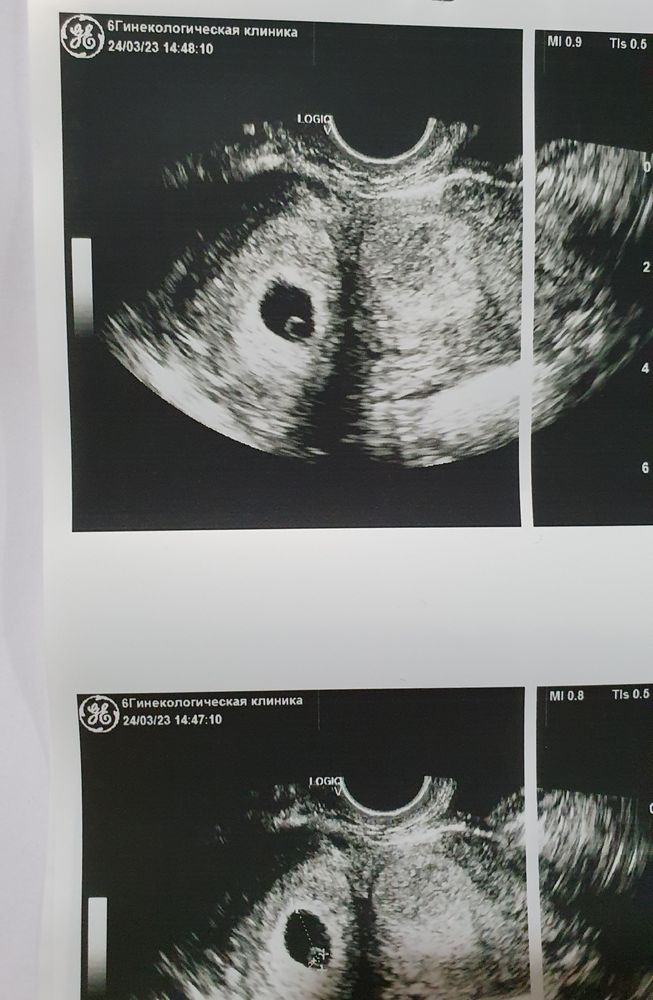

Первое узи

Срок - 6 недель с последних месячных, но овуляция была поздней, примерно на 19 ДЦ.

Сходила сегодня на приём и узи. Увидели ПЯ (15 мм) и ЖМ (2,6 мм). Эмбриончика еще не видно. Примерный срок по узи 5 недель. В итоге назначили следующее узи через 10 дней, чтобы уже увидеть эмбрион и послушать СБ.

Овуляция кстати была в правом яичнике (ЖТ 19 мм), беременность в правом роге. Гинеколог сказала, что второй рог может начать кровить, так как в нем эндометрий тоже разросся. Предупредила, что если такое случится, лучше поехать в стационар. В связи с этим назрел вопрос, у кого как протекала беременность с двурогой маткой? Были какие-то осложнения?